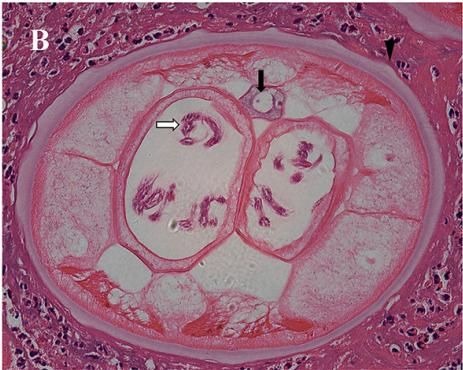

紧接着,我们联合病理科的专家们一同对老刘的病理结果进行了更为详细的分析。镜下,苏木精和伊红染色染色发现成虫被纤维结节包裹。诊断的关键特征有角皮层具有明显的横纹,表皮环(黑色三角)、包含卷曲的微丝蚴的成对子宫分支(白色箭头)、肠道(黑色箭头)。这些病理特征符合盘尾丝虫的虫体特征。

图2. 手术后病理镜检

A. 苏木精和伊红染色显示数条盘尾丝虫成虫,包括一个完整的纵切面的成年雌性成虫(×40倍);

B. 横剖面示盘尾丝虫被炎症细胞包围(×400倍)